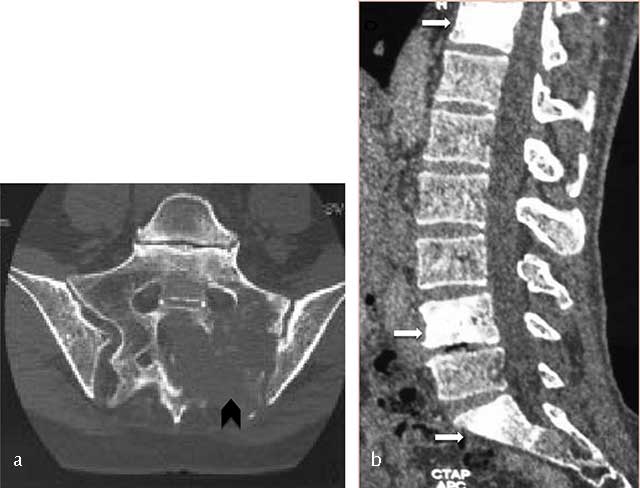

Figure 7

Lymphoma of the sacrum. Axial CT scan image shows a destructive lesion of sacrum extending through the left sacroiliac joint (arrowhead).